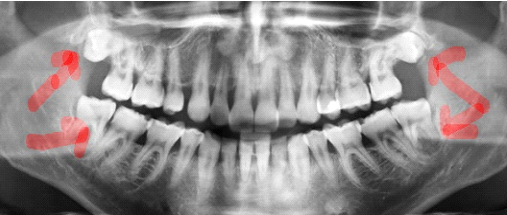

Na imagem abaixo temos os sisos superiores inclusos e os inferiores erupcionados,

porém com falta de espaço e indicação de extração, mesmo que apareçam em boca: